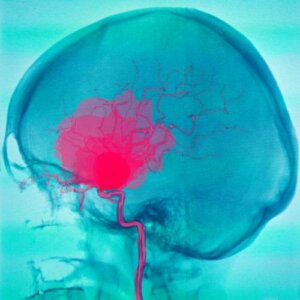

Lukinkalvonalaisessa verenvuodossa veri kerääntyy lukinkalvon ja pehmytkalvon väliseen tilaan. Veri on yleensä lähtöisin valtimoista ja verenvuoto voi johtua useista eri syistä. Yleisin lukinkalvonalaiseen verenvuotoon johtaneista syistä on aneurysman eli valtimon pullistuman repeämä, mutta joissakin tapauksissa verenvuoto voi johtua myös verisuonen epämuodostumista.

Aneurysmit voivat ilmetä päänsärkyinä tai epilepsiakohtauksina ennen niiden repeämää. Jopa kolmanneksessa aneurysman liittyvistä tapauksista repeytymiseen johtanut tekijä on emotionaalisella komponentilla varustettu fyysinen ponnistus tai pitkä altistuminen auringolle.

Kun aneurysma rikkoutuu, lukinkalvonalainen verenvuoto alkaa. Yleensä tätä tapahtuu 40- 60-vuotiailla aikuisilla. Verenvuodon alku on äkillinen ja vuodon seurauksena potilaalle ilmaantuu seuraavia oireita: